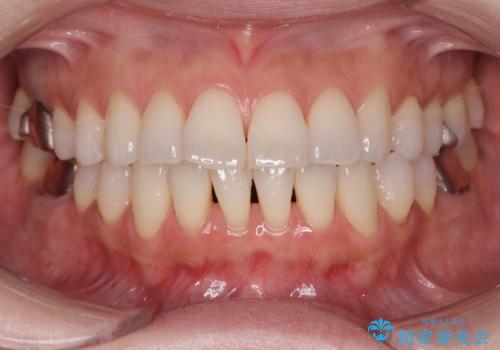

[ 非抜歯矯正 ] 歯を抜かずに出っ歯の治療

![[ 非抜歯矯正 ] 歯を抜かずに出っ歯の治療の症例 治療前](https://seimitsushinbi.jp/wp/wp-content/uploads/2025/03/IMG_6660-500x350.jpg?v=1741945892)

![[ 非抜歯矯正 ] 歯を抜かずに出っ歯の治療の症例 治療後](https://seimitsushinbi.jp/wp/wp-content/uploads/2025/03/IMG_7513-500x350.jpg?v=1741945816)